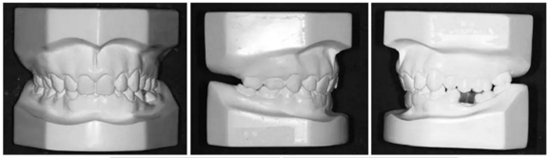

3.體格檢查:直面型,露齦笑,深覆合、合平面傾斜(Figure 1)。上中線偏右3mm,下中線偏左2mm。磨牙II類關(guān)系,左側(cè)尖牙II類關(guān)系,右側(cè)尖牙I類關(guān)系,左下第二磨牙低位咬合,右上前磨牙缺失。覆蓋率為100%,覆蓋度為4mm。咬合平面重度傾斜,左側(cè)向下移位(Figure 2、3)。

4.影像檢查:右上前磨牙和左下第二前磨牙缺失(Figure 4)。在另一名牙齒矯正醫(yī)師治療4年后,患者在19歲時(shí)被轉(zhuǎn)診給我們。他的咬合特征與他的初始狀態(tài)非常相似(Figure 5)